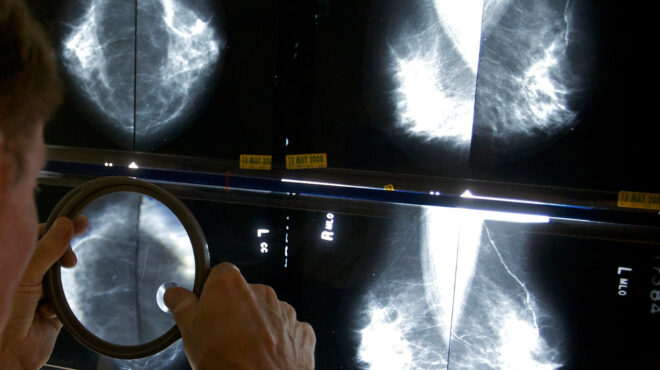

Τη δυνατότητα της Τεχνητής Νοημοσύνης να διαβάζει με «ασφάλεια» εξετάσεις για τον καρκίνο του μαστού ερευνά νέα σουηδική μελέτη, με τους επιστήμονες να διαπιστώνουν πως η ανίχνευση μέσω υπολογιστή μπορεί να αποδώσει όσο δύο ακτινολόγοι.

Οι επιστήμονες συμφωνούν ότι η Τεχνητή Νοημοσύνη προσφέρει μεγάλες προοπτικές στον έλεγχο του καρκίνου του μαστού, ωστόσο, θα χρειαστούν περισσότερες έρευνες για να διαπιστωθεί πλήρως αν θα μπορούσε να χρησιμοποιηθεί σε προγράμματα προσυμπτωματικών ελέγχων.

Στη νέα μελέτη, που δημοσιεύθηκε στο Lancet Oncology, συμμετείχαν περισσότερες από 80.000 γυναίκες από τη Σουηδία με μέση ηλικία 54 ετών.

Οι μισές από τις περιπτώσεις αξιολογήθηκαν από δύο ακτινολόγους, ενώ οι υπόλοιπες με τη χρήση Τεχνητής Νοημοσύνης και ακολούθησε ερμηνεία από έναν ή δύο ακτινολόγους.

Συνολικά, 244 γυναίκες από τον υποστηριζόμενο από την Τεχνητή Νοημοσύνη έλεγχο εντοπίστηκαν να έχουν καρκίνο, ενώ το ποσοστό των ψευδώς θετικών αποτελεσμάτων ανήλθε σε ποσοστό 1,5%, τόσο στην ομάδα της τεχνητής νοημοσύνης όσο και στην ομάδα που αξιολογήθηκε από ακτινολόγους.

Η επικεφαλής της έρευνας, Δρ Κριστίνα Λανγκ, δήλωσε ότι η τεχνητή νοημοσύνη έχει τη δυνατότητα να συνεισφέρει στον έλεγχο του καρκίνου του μαστού, συμβάλλοντας στην αντιμετώπιση των ελλείψεων σε ακτινολόγους που παρατηρούνται σε όλο τον κόσμο.

Ωστόσο, δήλωσε ότι χρειάζεται περισσότερη έρευνα στον τομέα αυτό για να κατανοηθούν πλήρως οι δυνατότητες και η σχέση κόστους-αποτελεσματικότητας.